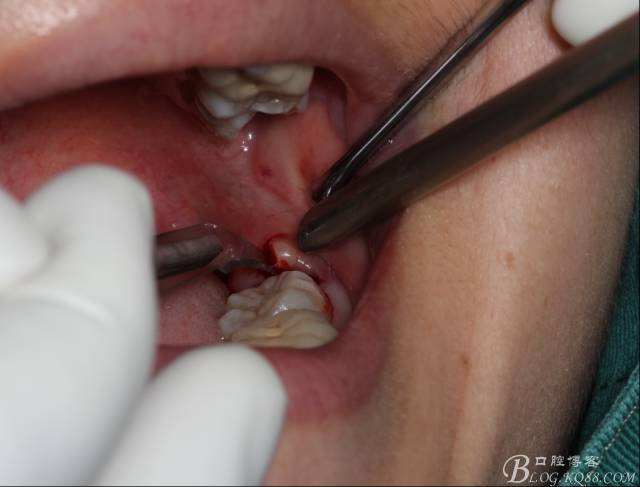

切開:角形切口,這個(gè)位置切開我喜歡更易操作12#刀。

640 (8).jpg